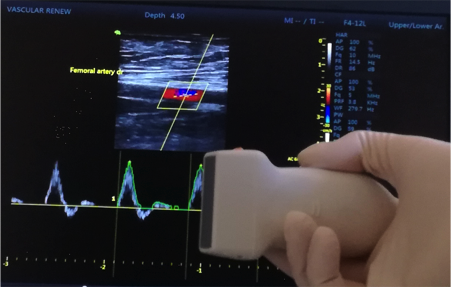

La Centrul Medical SILOȘI, punem accent pe tehnologie avansată și expertiză medicală. Realizăm ecografii Doppler de înaltă precizie, prin care putem analiza fluxul de sânge în timp real, detectând eventuale îngustări, blocaje, refluxuri venoase sau alte anomalii circulatorii.

Această investigație se bazează pe efectul Doppler, care permite măsurarea vitezei și direcției de circulație a sângelui, oferind informații esențiale pentru diagnosticarea și monitorizarea afecțiunilor vasculare. Totul se desfășoară rapid, fără durere, fără radiații și fără disconfort pentru pacient.

Cum se desfășoară investigația

Examinarea este rapidă, complet nedureroasă și nu necesită nicio pregătire specială. Pacientul este așezat confortabil, iar medicul aplică pe piele un gel transparent, care facilitează transmiterea undelor ultrasonore. Cu ajutorul unei sonde speciale, se scanează segmentele venoase ale membrelor inferioare (sau alte regiuni, în funcție de indicație), iar imaginea fluxului sanguin este afișată în timp real pe monitor.

Ecografia Doppler arterială este o metodă neinvazivă și nedureroasă care folosește ultrasunete pentru a examina fluxul sanguin prin arterele corpului, evidențiind viteza și direcția circulației.

Prin intermediul efectului Doppler, medicul poate identifica îngustări (stenoze), blocaje parțiale sau totale, precum și depuneri de placă de aterom pe pereții arteriali – principalele cauze ale bolii arteriale periferice.

Investigația permite vizualizarea în timp real a arterelor de la nivelul gâtului, brațelor sau picioarelor, oferind informații esențiale pentru stabilirea unui diagnostic precis și pentru monitorizarea tratamentului vascular.

Pacientul este poziționat confortabil, iar medicul aplică un gel transparent pe zona investigată pentru a facilita transmiterea ultrasunetelor. Cu ajutorul sondei ecografice, se analizează fluxul sanguin prin arterele principale și secundare.

Examinarea durează în general 20-40 de minute, în funcție de zona investigată, iar imaginile sunt afișate în timp real pe monitor. Medicul poate observa: